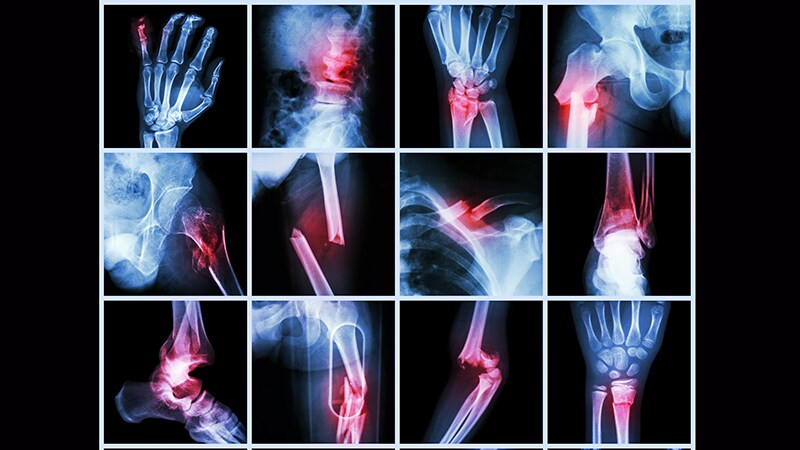

Osteoporosis

ASBMR 2023Bariatric Surgery Linked to Fracture Risk -

ASBMR 2023Higher Fracture Risk Not Seen With SGLT2 Inhibitors -

ASBMR 2023Premenopausal Osteoporosis: What to Do After Denosumab -

ASBMR 2023Fractures Beget Fractures at Any Age